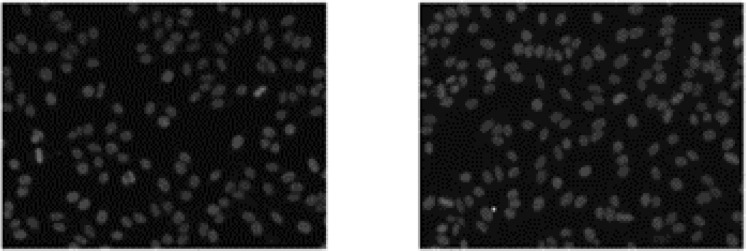

Objective: The diagnosis of autoimmune disorders, particularly through the Anti-Nuclear Antibodies (ANA) Indirect Immunofluorescence (IIF) test utilising human epithelial type-2 (HEp-2) cells, presents a formidable challenge due to the subjective nature of pathologists' analysis. In response, this study proposes an innovative automated approach that integrates deep learning, advanced image processing, guided Hep-2 Cell, and mitotic cell instance segmentation.

Methods: Leveraging the ICPR 2016 dataset for training and evaluation, this research encountered an initial challenge of dataset imbalance, with a significantly lower number of mitotic cells compared to HEp-2 Homogenous cells. To overcome this, data augmentation techniques were strategically employed to ensure a balanced representation.

Results: In Experiment 1, the Detectron2 model achieved an overall mean Average Precision of 54% for segmentation masks and 55% for bounding boxes. In Experiment 2, the YOLOv8n model demonstrated an impressive overall Mean Average Precision score of 94% for bounding boxes and 93% for segmentation masks, showcasing its exceptional efficacy in detecting HEp-2 cells and mitotic cells. The instance segmentation provided a more granular analysis, revealing the count of cells in each class, further highlighting the model's proficiency in diagnosing autoimmune diseases.

Conclusion: This study establishes a reliable and automated method for HEp-2 Homogenous cell detection, addressing the ongoing challenges in autoimmune disease diagnosis and contributing significantly to the ongoing revolution in this critical field.